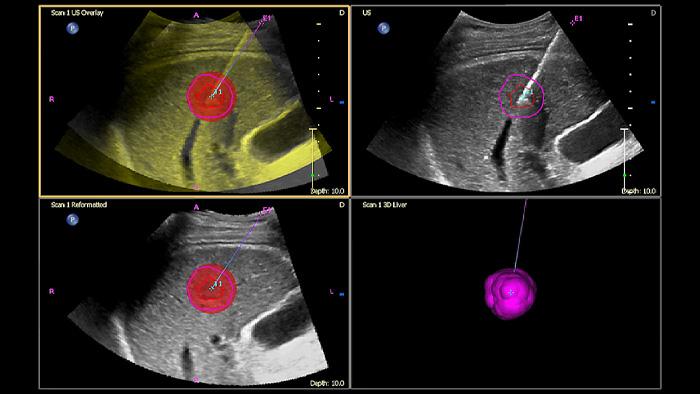

Tome decisiones fiables incluso en casos diagnósticos complejos gracias a las funciones de navegación guiada por aguja y fusión de imágenes de Philips. El flujo de trabajo agilizado permite a los médicos conseguir una fusión rápida y efectiva de imágenes TC/RM/PET mediante ecografía en tiempo real, mientras que la navegación guiada por aguja permite guiar la biopsia en lesiones pequeñas o de difícil acceso.2.

Mediante el uso de la función de contorno tumoral, los usuarios pueden planificar y dirigir las lesiones con una herramienta semiautomatizada que ayuda a trazar un contorno 3D alrededor de una estructura de interés, lo que puede mejorar la guía del procedimiento en casos difíciles en los que la lesión no se pueda visualizar fácilmente.